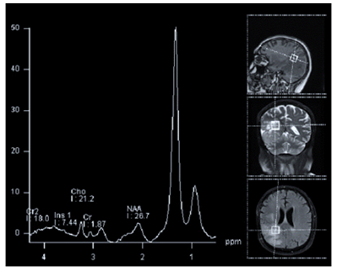

Observe a figura a seguir.

Em relação à figura acima, é correto afirmar que